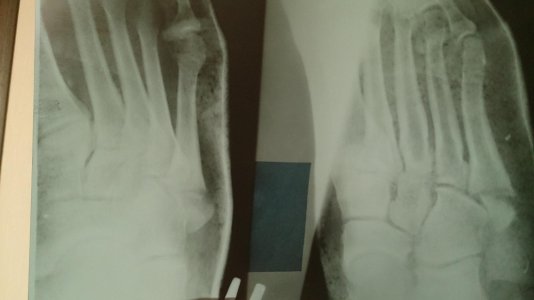

Добрый день!

Неделю назад оступился на лестнице, в итоге перелом основания пятой плюсневой кости. Травматолог который смотрел первично, сказал, что операция не требуется, срастется и так, наложили гипс.

Через неделю, на повторном приеме, врач был другой и он сразу же отправил на снимок и госпитализацию в городскую больницу, для выполнения операции. Врачи в городской больнице посмотрели снимок и сказали, что операция не требуется. Что в итоге мне делать, срастется ли такой перелом, я до сих пор точно не знаю. Свежий снимок во вложении.

Помогите, пожалуйста!